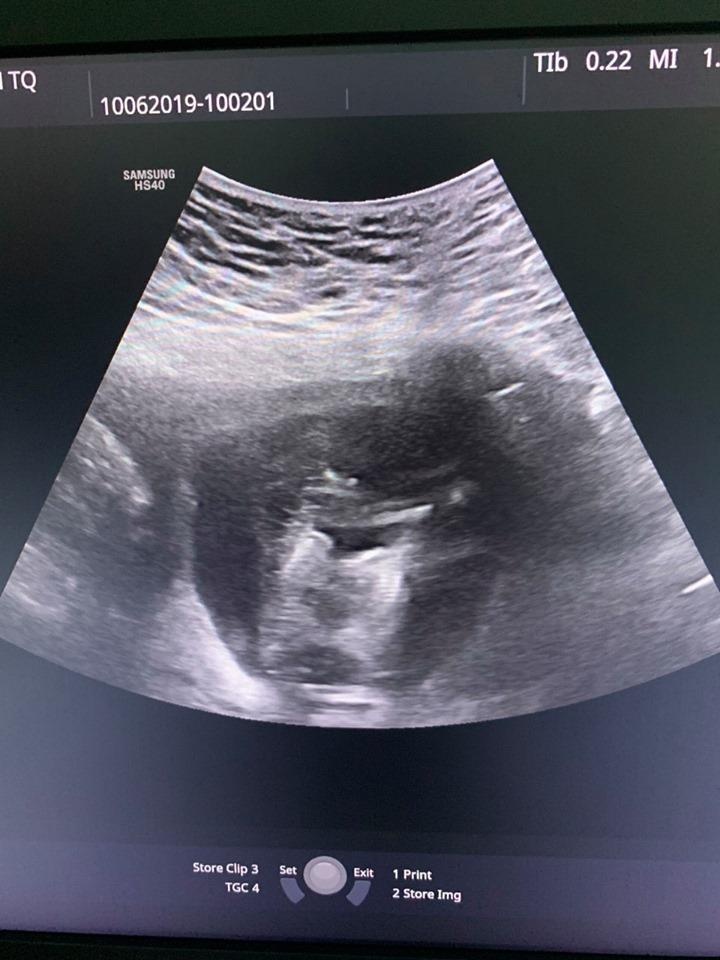

Kết quả kiểm tra cho thấy chị P. đang mang song thai ở tuần thứ 12. Tuy nhiên, 2 thai dính nhau từ phần ngực xuống đến bụng, chung một quả tim và đều có tăng khoảng sáng sau gáy (2,5 mm và 8,0 mm).

| Hình ảnh siêu âm của thai phụ. Ảnh: BVCC. |